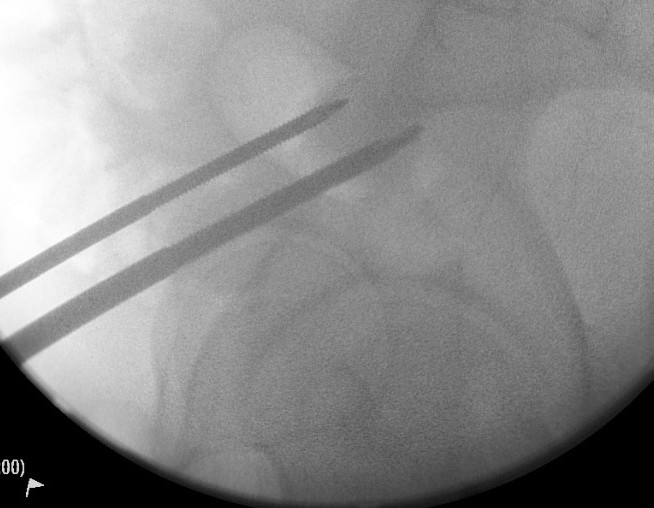

Entry point of steinmann pins

- intersection of 2 lines

- line parallel with femur / line back from ASIS